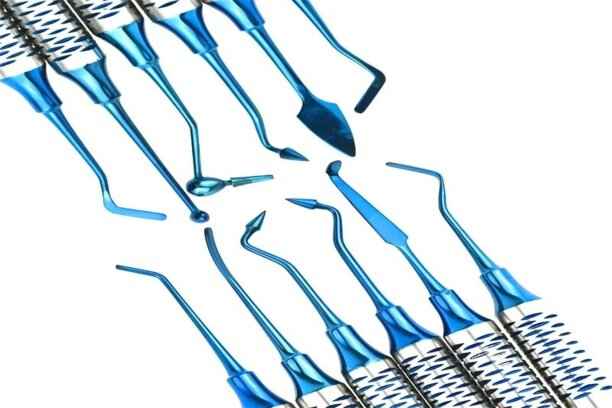

أدوات حشو الأسنان

تشمل أدوات حشو الأسنان الأساسية:

- أدوات الحفر الدقيقة لإزالة التسوس بدقة دون الإضرار بالأنسجة.

- أدوات تشكيل وصقل الحشو للحصول على سطح أملس ومتناسق مع السن الطبيعي.

- أدوات قياس الإطباق لضمان عدم وجود ضغط زائد على الأسنان المجاورة.

- أجهزة التعقيم الحديثة لضمان نظافة وسلامة الأدوات قبل الاستخدام.

- أجهزة الليزر لتحضير السن وتقليل الألم وزيادة دقة العملية في بعض الحالات.